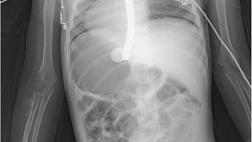

После этого выполнена интубация трахеи. При контрольной рентгенограмме органов грудной клетки осложнений не выявлено. После завершения курса антибактериальной терапии пациент был выписан из стационара.